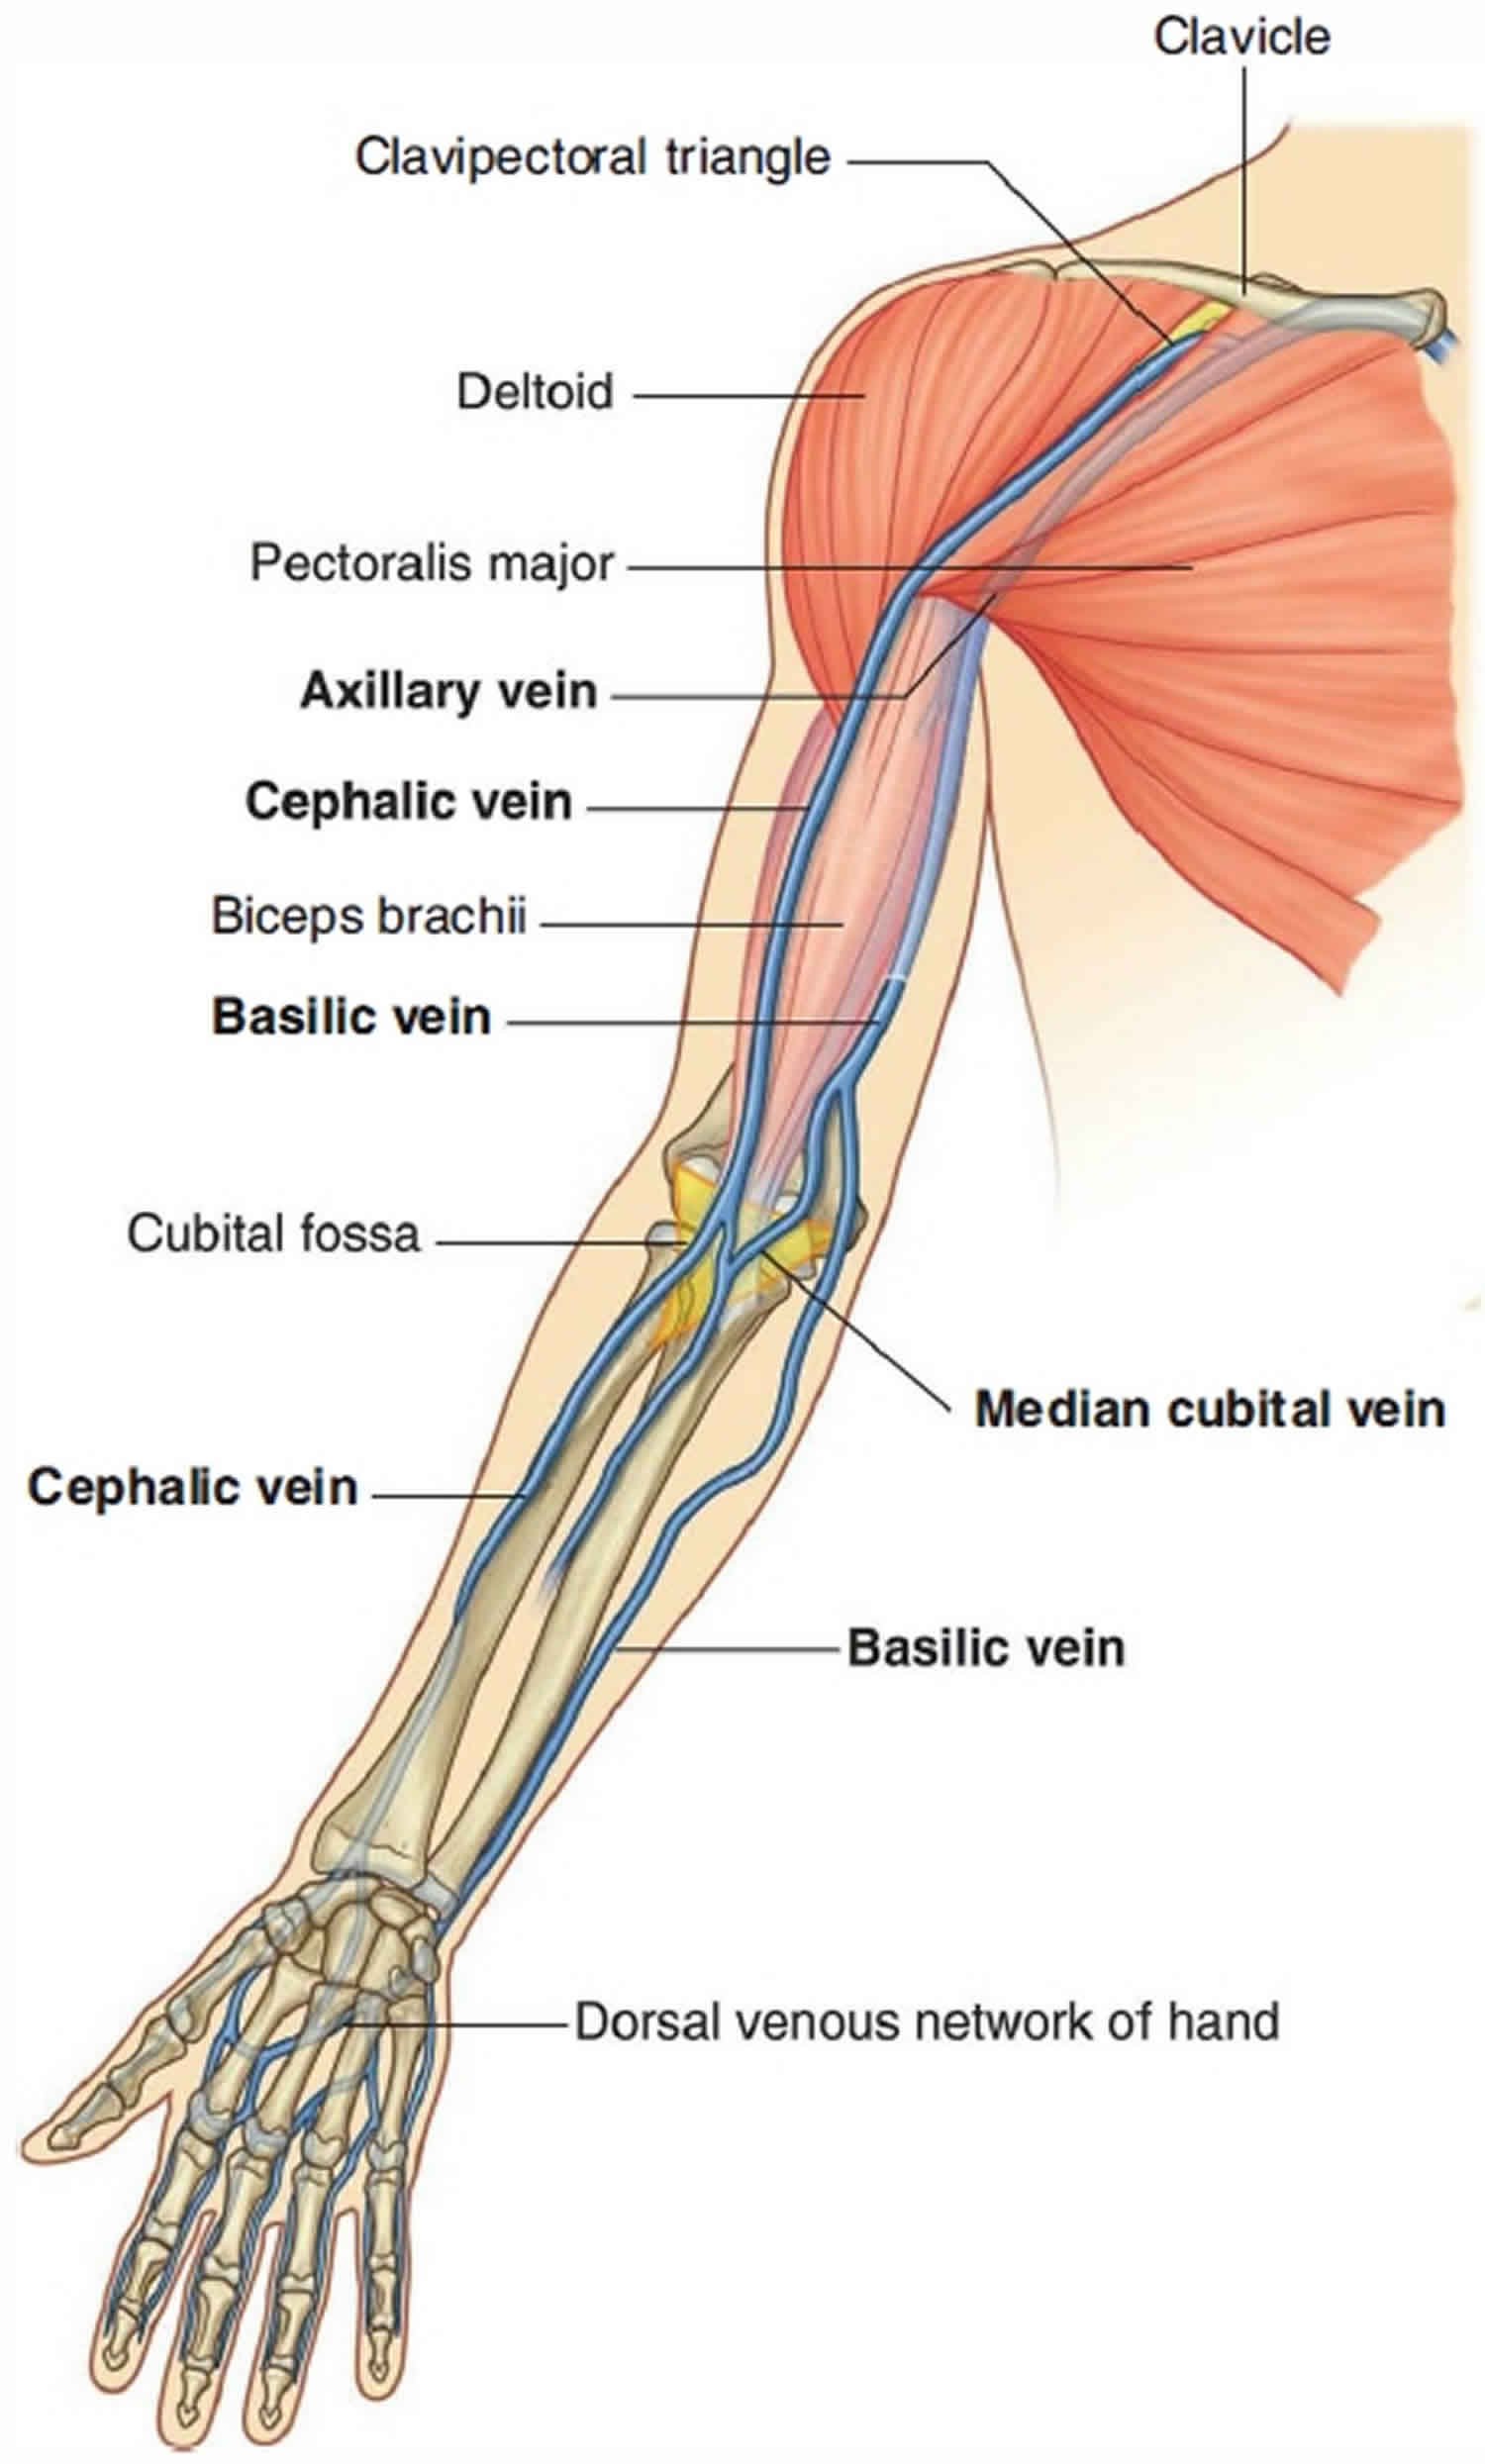

Anatomy, Shoulder And Upper Limb, Veins - StatPearls - NCBI Bookshelf

veins vein upper cephalic limb ncbi statpearls

Image Of The Superficial Veins Of Arm And Forearm

vein cephalic veins arm access forearm superficial accessory cardiovascular triceps modernheal important whatsapp twitter anatomicvariants anatomyatlases

Arm: Anatomy [+video] - Lecturio Medical

arm vein veins groove deltopectoral muscles anatomy shoulder where lecturio hand aspect axillary deltoid pectoralis empties between through into

Anatomy, shoulder and upper limb, veins. Image of the superficial veins of arm and forearm. Vein cephalic veins arm access forearm superficial accessory cardiovascular triceps modernheal important whatsapp twitter anatomicvariants anatomyatlases